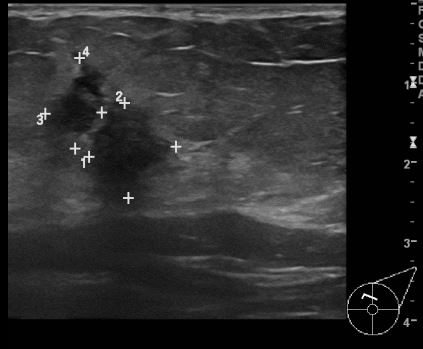

상기환자 좌측 유방에 만져지는 멍울로 내원하신 50대 여성분으로 좌측유방 만져지는

멍울 조직검사 시행하여 좌측 유관암 진단 되었습니다.